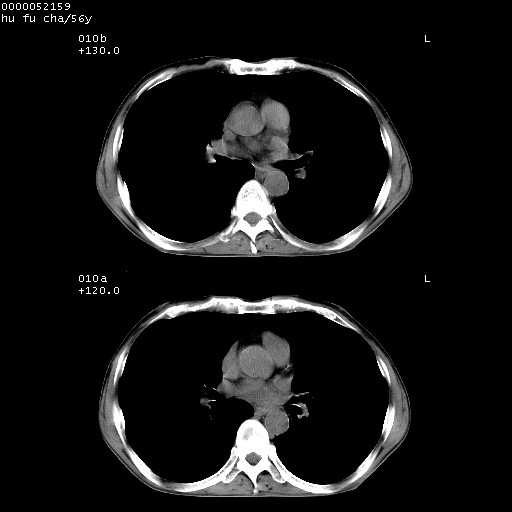

以下是引用zsl6918在2008-8-25 22:47:00的发言:[br]胸骨,胸椎及肋骨均可见多发转移表现,肝内低密度结节不除外转移。原发灶可能在右肺。双侧可见支扩表现。